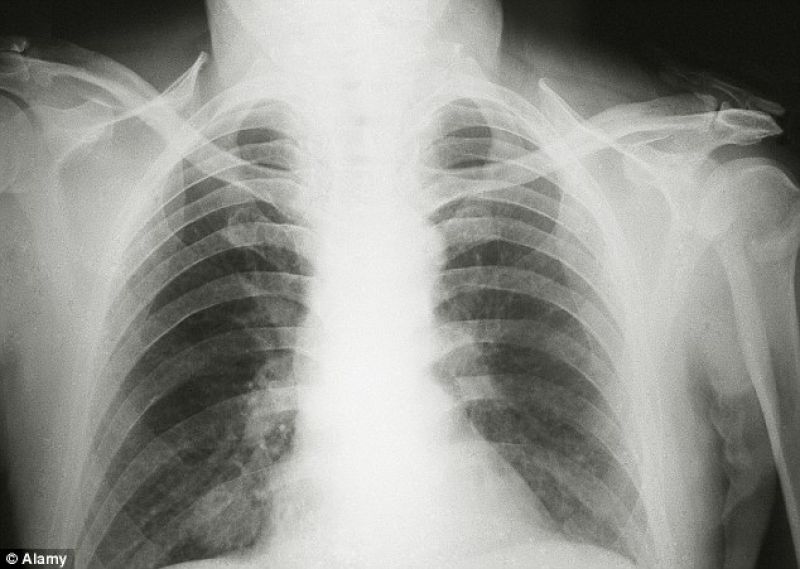

ਨਵੀਂ ਦਿੱਲੀ: ਆਮ ਤੌਰ ਉੱਤੇ ਅਜਿਹਾ ਮੰਨਿਆ ਜਾਂਦਾ ਹੈ ਕਿ ਸਿਗਰੇਟ ਪੀਣ ਕਰਣ ਹੀ ਲੋਕਾਂ ਫੇਫੜੇ ਦੇ ਕੈਂਸਰ ਨਾਲ ਪੀੜਤ ਹੁੰਦੇ ਹਨ।ਪਰ ਇਹ ਵੀ ਮੰਨਿਆ ਜਾਂਦਾ ਹੈ ਕੇ ਇਸ ਬਿਮਾਰੀ ਦੇ ਪਿੱਛੇ ਹਵਾ ਪ੍ਰਦੂਸ਼ਣ ਨੂੰ ਮੁਖ ਕਾਰਨ ਮੰਨਿਆ ਜਾਂਦਾ ਹੈ। ਕਿਹਾ ਜਾ ਰਿਹਾ ਹੈ ਕੇ ਪ੍ਰਦੂਸ਼ਣ ਦੇ ਕਾਰਨ ਲੋਕ ਫੇਫੜੇ ਦੇ ਕੈਂਸਰ ਨਾਲ ਪੀੜਤ ਹੋ ਰਹੇ ਹਨ। ਦਸਿਆ ਜਾ ਰਿਹਾ ਹੈ ਕਿ ਫੇਫੜੇ ਦੇ ਕੈਂਸਰ ਨਾਲ ਪੀੜਤ ਮਰੀਜਾਂ ਵਿੱਚ ਹਰ ਦੂਜਾ ਵਿਅਕਤੀ ਨਾਨ ਸਮੋਕਰ ਹੈ।

ਲੋਕ ਪ੍ਰਦੂਸ਼ਣ ਦੇ ਕਾਰਨ ਹੀ ਇਸ ਬਿਮਾਰੀ ਦਾ ਸ਼ਿਕਾਰ ਹੋ ਰਹੇ ਹਨ। ਤੁਹਾਨੂੰ ਦਸ ਦੇਈਏ ਕੇ ਗੰਗਾਰਾਮ ਹਸਪਤਾਲ ਦੇ ਸੇਂਟਰ ਫਾਰ ਚੇਸਟ ਸਰਜਰੀ ਦੇ ਪ੍ਰਧਾਨ ਡਾ . ਅਰਵਿੰਦ ਕੁਮਾਰ ਨੇ ਕਿਹਾ ਕਿ ਮਾਰਚ 2014 ਤੋਂ ਜੂਨ 2018 ਦੇ ਵਿਚ ਇਲਾਜ ਲਈ ਪੁੱਜੇ ਫੇਫੜੇ ਦੇ ਕੈਂਸਰ ਨਾਲ ਪੀੜਤ 150 ਮਰੀਜਾਂ ਉੱਤੇ ਜਾਂਚ ਕੀਤੀ ਗਈ ਹੈ। ਜਿੰਨ੍ਹਾਂ `ਚ ਪਾਇਆ ਗਿਆ ਕਿ 50 ਫੀਸਦ ਮਰੀਜ ਸਿਗਰਟ ਪੀਂਦੇ ਹਨ , ਜਦੋਂ ਕਿ 50 ਫੀਸਦ ਲੋਕ ਇਸ ਦਾ ਸੇਵਨ ਸੇਵਨ ਨਹੀਂ ਕਰਦੇ।

ਨਾਲ ਹੀ ਉਹਨਾਂ ਦਾ ਕਹਿਣਾ ਹੈ ਕੇ ਮਰੀਜਾਂ ਦੇ ਪਰਵਾਰ ਵਿਚ ਵੀ ਕੋਈ ਸਿਗਰੇਟ ਦਾ ਸੇਵਨ ਨਹੀਂ ਕਰਦਾ। ਪੜ੍ਹਾਈ ਵਿੱਚ ਪਾਇਆ ਗਿਆ ਕਿ 21 ਫੀਸਦ ਮਰੀਜਾਂ ਦੀ ਉਮਰ 50 ਸਾਲ ਵਲੋਂ ਘੱਟ ਸੀ । ਇਹਨਾਂ ਵਿਚੋਂ 3 . 3 ਫੀਸਦ ਮਰੀਜਾਂ ਦੀ ਉਮਰ 21 ਵਲੋਂ 30 ਸਾਲ ਦੇ ਵਿੱਚ ਅਤੇ 5 . 3 ਫੀਸਦ ਦੀ ਉਮਰ 31 ਵਲੋਂ 40 ਸਾਲ ਦੇ ਵਿੱਚ ਸੀ । ਪਹਿਲਾਂ ਦੀ ਤੁਲਣਾ ਵਿੱਚ ਤੀਵੀਂ ਮਰੀਜਾਂ ਦੀ ਗਿਣਤੀ ਵੀ ਵਧੀ ਹੈ ।

33 . 3 ਫੀਸਦ ਮਰੀਜਾਂ ਦੀ ਉਮਰ 51 - 60 ਸਾਲ ਅਤੇ 30 ਫੀਸਦ ਮਰੀਜਾਂ ਦੀ ਉਮਰ 61 - 70 ਸਾਲ ਸੀ । ਪੁਰਖ ਅਤੇ ਤੀਵੀਂ ਮਰੀਜਾਂ ਦਾ ਅਨਪਾਤ 3 . 8 : 1 ਪਾਇਆ ਗਿਆ। ਡਾ . ਅਰਵਿੰਦ ਨੇ ਕਿਹਾ ਕਿ ਪਹਿਲਾਂ ਕਰੀਬ 90 ਫੀਸਦ ਲੋਕਾਂ ਨੂੰ ਇਹ ਰੋਗ ਸਿਗਰੇਟ ਪੀਣ ਦੇ ਕਾਰਨ ਹੁੰਦਾ ਸੀ । ਬਾਅਦ ਵਿੱਚ ਇਹ ਗਰਾਫ ਡਿੱਗ ਕੇ 70 - 80 ਫੀਸਦ ਉੱਤੇ ਆਇਆ ।ਉਹਨਾਂ ਦਾ ਕਹਿਣਾ ਹੈ ਕੇ ਪ੍ਰਦੂਸ਼ਣ ਦੇ ਕਾਰਨ ਲੋਕਾਂ ਦਾ ਫੇਫੜਾ ਕਾਲ਼ਾ ਪੈਂਦਾ ਜਾ ਰਿਹਾ ਹੈ ।

ਡਾਕਟਰ ਕਹਿੰਦੇ ਹਨ ਕਿ ਦੇਸ਼ ਵਿੱਚ ਫੇਫੜੇ ਦੇ ਕੈਂਸਰ ਦੇ ਹਰ ਸਾਲ 60 - 70 ਹਜਾਰ ਮਾਮਲੇ ਸਾਹਮਣੇ ਆਉਂਦੇ ਹਨ । ਦਿੱਲੀ ਸਹਿਤ ਕਈ ਸ਼ਹਿਰਾਂ ਵਿੱਚ ਪ੍ਰਦੂਸ਼ਣ ਇੰਨਾ ਵੱਧ ਗਿਆ ਹੈ ਸਿਗਰਟ ਪੀਣ ਜਾਂ ਨਹੀਂ ਪੀਣ ਦਾ ਅੰਤਰ ਮਿਟ ਗਿਆ ਹੈ । ਜਨਮ ਦੇ ਬਾਅਦ ਤੋਂ ਹੀ ਬੱਚਾ 10 ਸਿਗਰਟ ਦੇ ਬਰਾਬਰ ਪ੍ਰਦੂਸ਼ਿਤ ਹਵਾ ਸਾਹ ਦੇ ਰੂਪ ਵਿੱਚ ਲੈ ਰਿਹਾ ਹੈ । ਇਸ ਲਈ ਲੋਕ ਨਹੀਂ ਚਾਹੁੰਦੇ ਹੋਏ ਵੀ ਸਿਗਰੇਟ ਪੀਣਾ ਕਰ ਰਹੇ ਹਨ। ਨਾਲ ਇਹ ਵੀ ਕਿਹਾ ਜਾ ਰਿਹਾ ਹੈ ਕੇ ਜੇਕਰ ਪ੍ਰਦੂਸ਼ਣ ਨੂੰ ਨਿਅੰਤਰਿਤ ਕਰਣ ਲਈ ਕਾਰਗਰ ਕਦਮ ਨਹੀਂ ਚੁੱਕੇ ਗਏ ਤਾਂ ਇਸ ਦੇ ਭਿਆਨਕ ਨਤੀਜੇ ਹੋਣਗੇ।